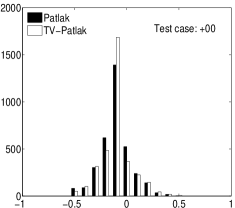

In the images shown in the figures we illustrate the calculated uptake rates of the FDG. Images for the CMRGlc can be obtained by directly scaling . In figure 1 we compare the result of using Patlak and TV-Patlak for estimating the uptake rates with respect to no noise, noise in the input function, Poisson noise in the sinogram, and finally with respect to the case in which the irreversibility assumption is violated but without noise in the sinogram or input data. In each case the histogram of the relative errors is given on the left, the Patlak image in the middle and the TV-Patlak on the right. The different scales in the histograms are due to the total number of results illustrated. When there is no noise (triples and ) the histogram illustrates results over all voxels but only one simulation, while for the noisy simulations the results are for all voxels over all realizations of the noise. The TV-Patlak images are more homogeneous in all cases and the relative errors are smaller. The figures clearly show the improvements of employing the TV-Patlak method as compared to using Patlak independently for each voxel. This is confirmed in figure 2 in which images with noise in the sinogram, positive and different noise levels in the input function are shown.

Quantitative measurements, confirming the illustrations, are presented in table 3. There we also present the results for conventional Patlak’s method with post-smoothing by two standard filters:

Consistent with the observation in [21, 16], we find that violation of the Patlak assumption, , introduces about bias; when but for . The rows (std) and “# 10% (#15%)” provide complementary supporting information, indicating that the TV is minimized by TV-Patlak; as compared to Patlak, Patlak-GF and Patlak-MF the number of voxels with larger error is reduced. In particular, we emphasize that TV-Patlak provides a better noise removal mechanism than popular post-filtering approaches.

In figures 3 and 4 we illustrate the uptake rates and relative error in the uptake rates, respectively, calculated by Patlak, TV-Patlak, Patlak-GF and Patlak-MF for one simulated data case , i.e. , noise in the input function and Poisson noise in the sinograms. The uptake rate image generated by Patlak-MF is visually smoother than that by TV-Patlak, but the equivalent histograms show that the relative error is higher for Patlak-MF than for TV-Patlak; the Patlak-MF image is over-smoothed.